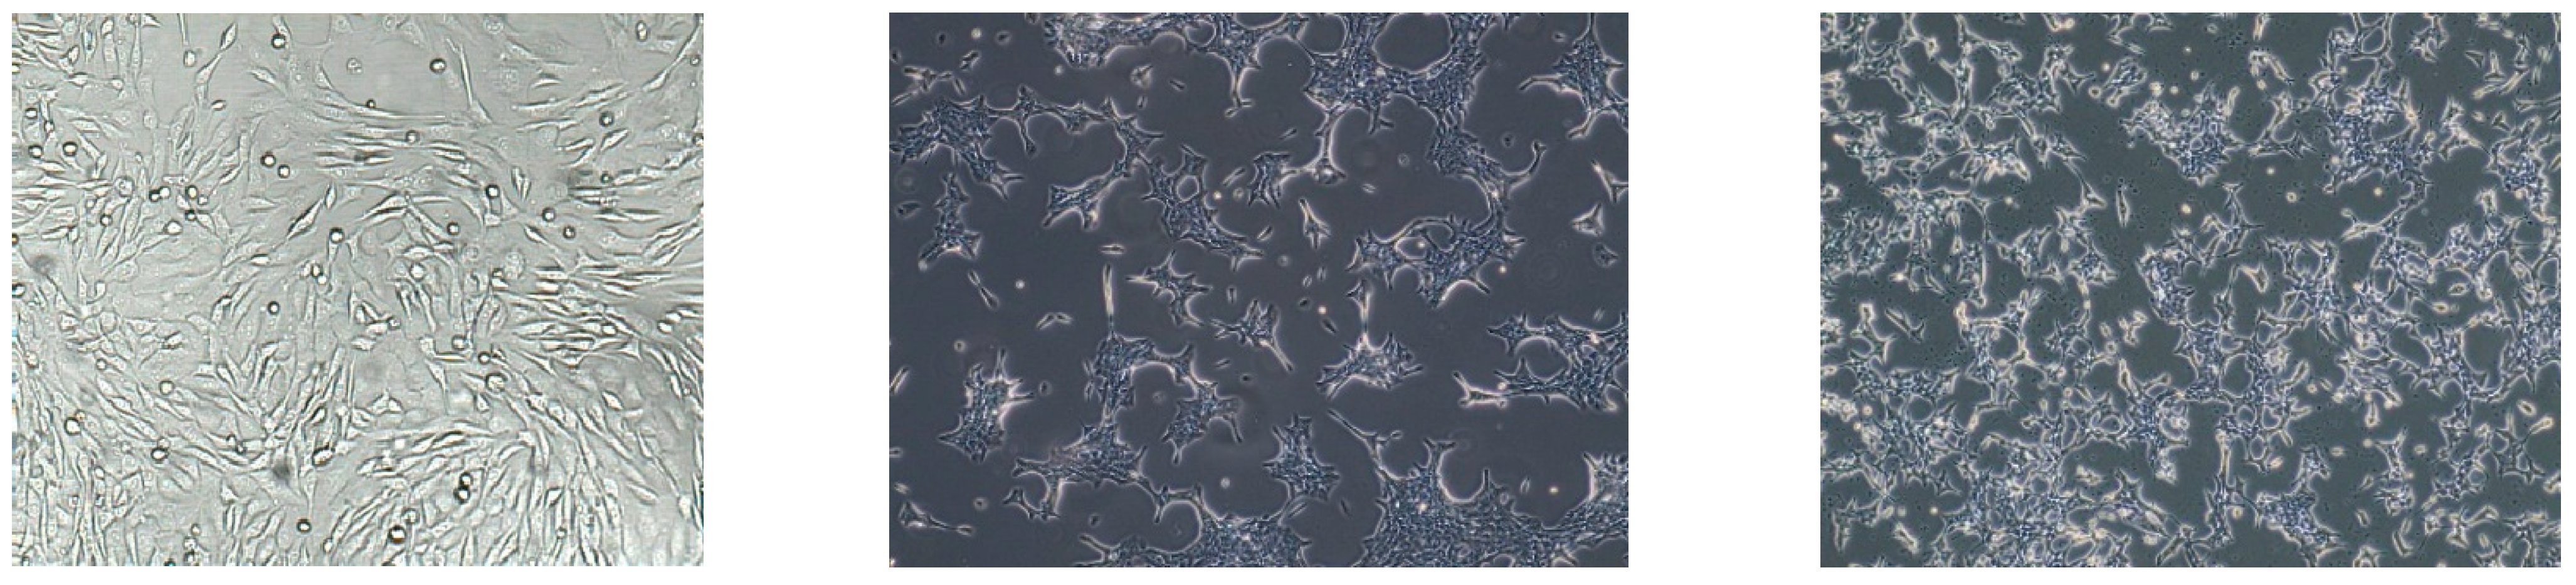

4.1. Cell Culture